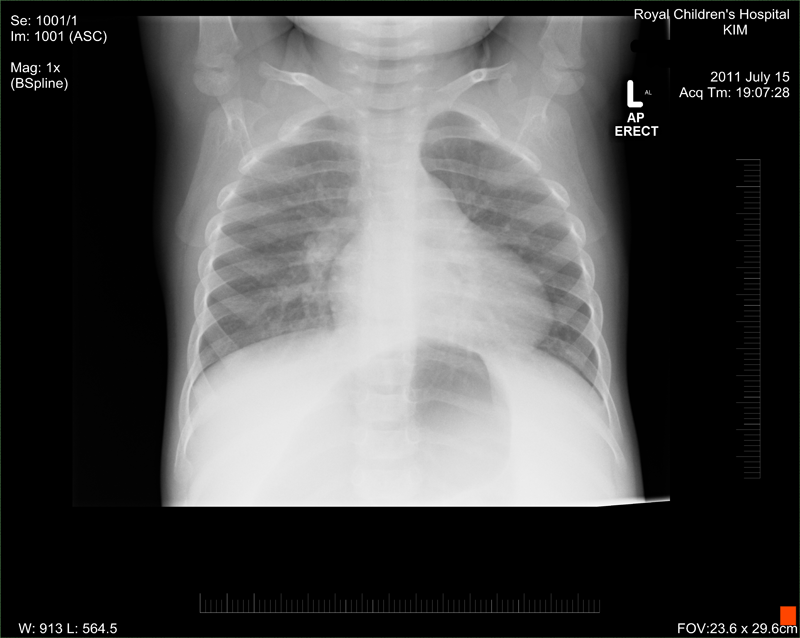

Emergency Royal Children's Hospital emergency organise an X-ray and some blood tests etc. The X-ray confirms a mass but it is not clear what it is, it only tells that there is something wrong. Later they organise her to be admitted. (We didn't know it but from that day on the hospital was becoming our new home.)